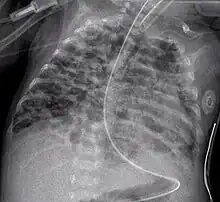

Chest radiograph

A chest radiograph, called a chest X-ray (CXR), or chest film, is a projection radiograph of the chest used to diagnose conditions affecting the chest, its contents, and nearby structures. Chest radiographs are the most common film taken in medicine.

Chest radiographs are used to diagnose many conditions involving the chest wall, including its bones, and also structures contained within the thoracic cavity including the lungs, heart, and great vessels. Pneumonia and congestive heart failure are very commonly diagnosed by chest radiograph. Chest radiographs are also used to screen for job-related lung disease in industries such as mining where workers are exposed to dust.[3]